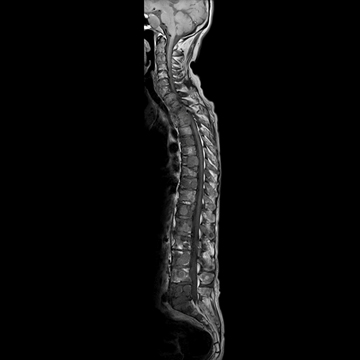

全脊椎

T1 TSE, 448 matrix

T2 STIR, 384 matrix,